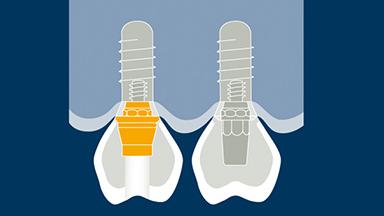

所有种植修复体的设计都应基于修复计划,并应满足所有相关的设计因素。大多数种植体固定义齿(或 FDP)的设计有许多共同点,以合理的设计遵循这些共同点很有帮助。第一要点是选择 FDP 的类型和方案。下一要点是选择固位方式,然后是考虑所需的外部和内部结构,以满足美观、功能和强度等因素。本模块将依次探讨每个设计要点。本网络学院设有单独且更详细的单元,将以现有模块为基础,阐述 FDP 修复材料、基台和种植体的选择。

- 固位方法的选择

- 外部设计

- 内部设计